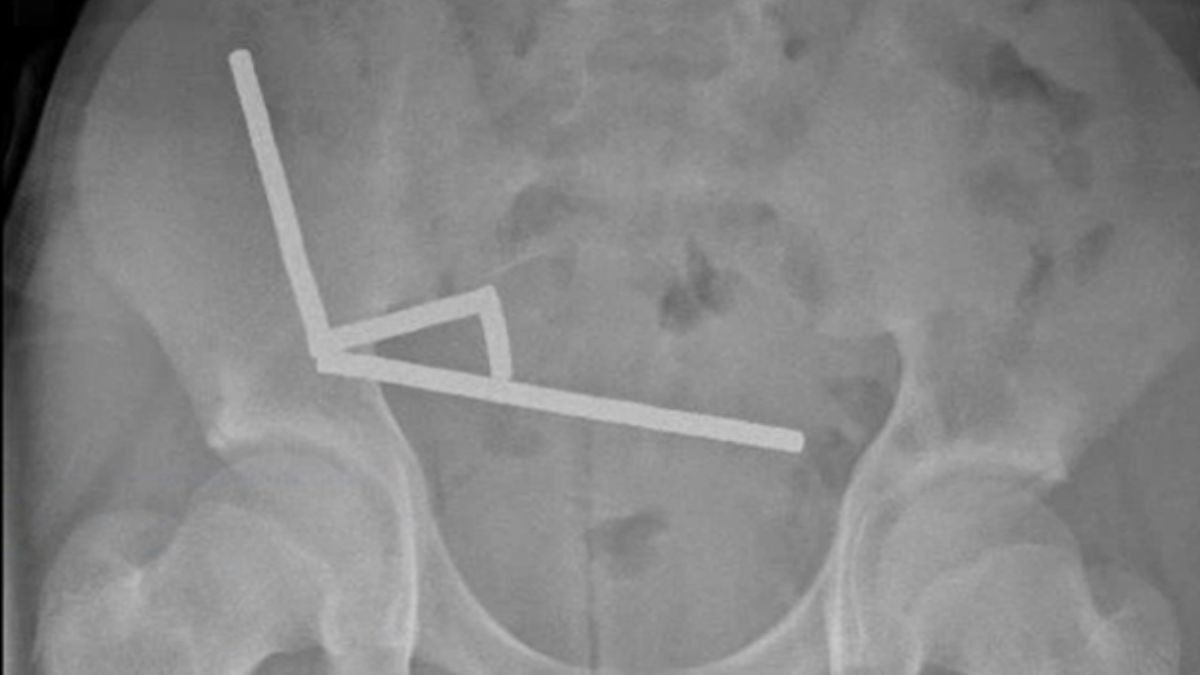

Jovem neozelandês perde parte do intestino após engolir quase 200 ímãs

Caso dramático acende alerta sobre o risco de ímãs de alta potência vendidos online e levanta debates sobre a dificuldade de fiscalização de ...